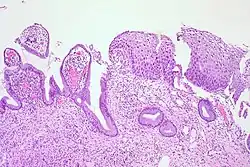

_normal_squamous_epithelium.jpg)

Historically, abnormal changes of cervical epithelial cells were described as mild, moderate, or severe epithelial dysplasia. In 1988 the National Cancer Institute developed "The Bethesda System for Reporting Cervical/Vaginal Cytologic Diagnoses".[12] This system provides a uniform way to describe abnormal epithelial cells and determine specimen quality, thus providing clear guidance for clinical management. These abnormalities were classified as squamous or glandular and then further classified by the stage of dysplasia: atypical cells, mild, moderate, severe, and carcinoma.[13]

CIN is classified in grades:[14]

| Histology Grade | Corresponding Cytology | Description | Image |

|---|---|---|---|

| CIN 1 (Grade I) | Low-grade squamous intraepithelial lesion (LSIL) |

|

| CIN 2/3 | High-grade squamous intraepithelial lesion (HSIL) |

| CIN 2 (Grade II) |

![]() | |

| CIN 3 (Grade III) |

![]() |